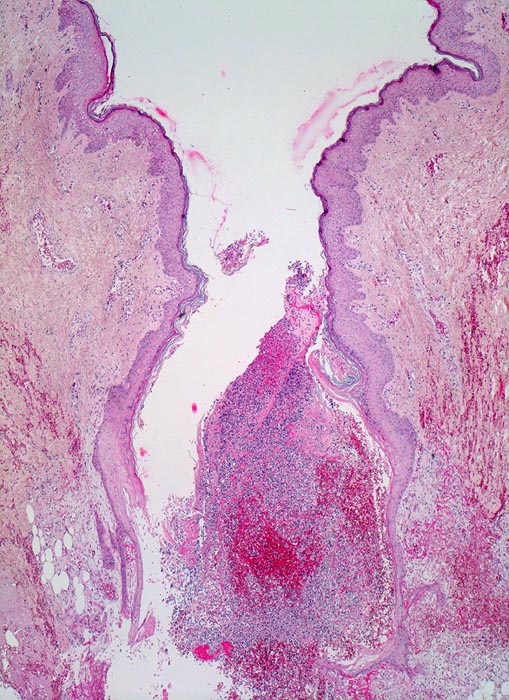

Wundheilung

Entzündung / Reparatur

Haut, Rumpf

Spaltförmiger Defekt des Plattenepithels, der sich fortsetzt in die darunterliegende Cutis. Der Spalt ist angefüllt mit Blut, Fibrin, Detritus (vorläufiger Propf). In den obersten Schichten massenhaft neutrophile Lenkozyten.

6 Tage alte Wunde am Abdomen nach Laparotomie.

Noch keine wesentliche Pflasterepithel-Regeneration möglicherweise als Ausdruck einer Wundheilungsstörung.